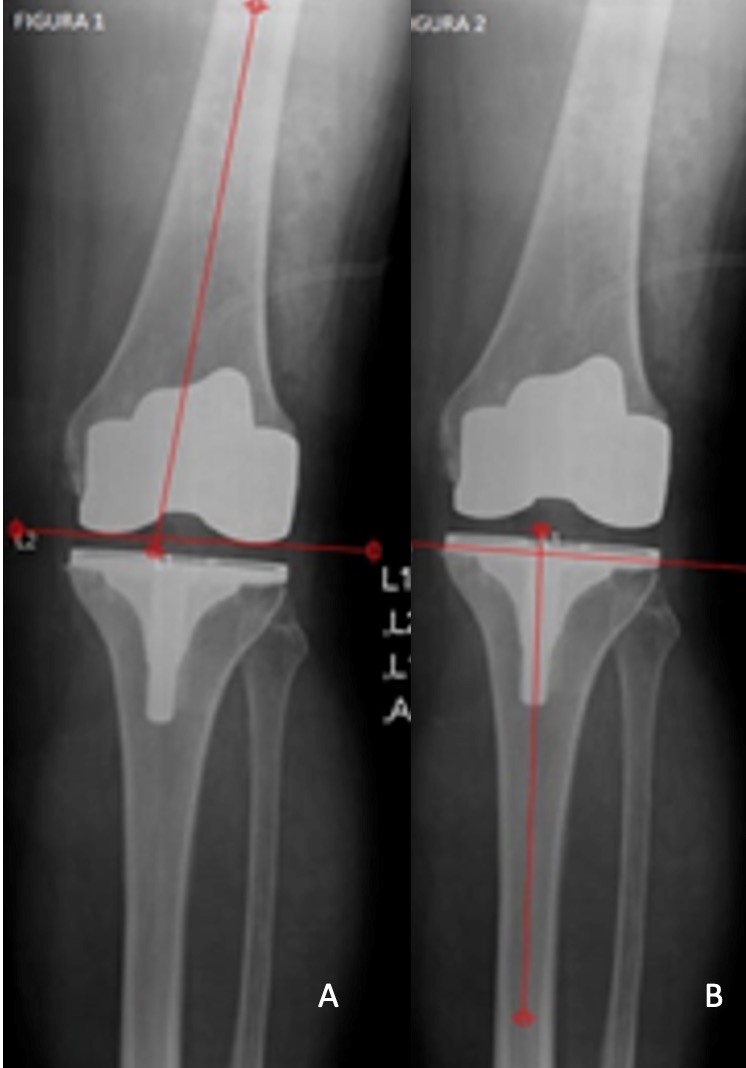

Foram analisadas as imagens de radiografias do joelho operado obtidas no pós-operatório imediato em ântero-posterior (AP) e perfil, bem como as imagens em AP e perfil do joelho com carga, realizadas com 3 meses de seguimento clínico, conforme protocolo da instituição. Os exames de imagem foram avaliados por um único observador membro do grupo de cirurgia do joelho. A análise radiográfica foi realizada de forma cega sem identificação do paciente. O software utilizado para o estudo foi o mDicomViewer 3.0 (Microdata, RJ-Brasil, 2007). O alinhamento coronal e sagital foram determinados pela medição de cinco ângulos radiográficos.15 O primeiro foi avaliado na radiografia em AP. Essa análise foi feita através de um ângulo formado pela superfície distal do componente femoral e o eixo da diáfise do fémur, além de um segundo ângulo formado entre o planalto tibial e o eixo da diáfise da tíbia (figura 2 A-B). Além disso, analisamos o ângulo tibio-femoral formado entre os eixos anatómicos do fémur e da tíbia (figura 3). A avaliação do alinhamento no plano sagital foi realizada através da radiografia em perfil, determinando-se o ângulo entre a parte mais distal da superfície de fixação femoral e o eixo da diáfise do fêmur (figura 4). De forma similar, a avaliação do alinhamento da tíbia nessa incidência corresponde ao ângulo entre o planalto tibial e o eixo da diáfise da tíbia (figura 5). O alinhamento patelofemoral não foi avaliado.

Figura 2: A: Ângulo formado pela superfície distal do componente femoral e o eixo da diáfise do fêmur. B: Ângulo formado entre a bandeja tibial e o eixo da diáfise da tíbia.